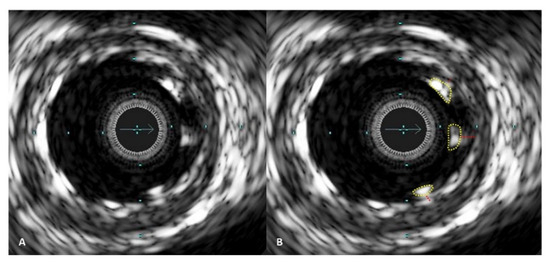

Before performing PCI, IVUS was utilized to determine the ideal stent implantation spots, aiming for locations with a plaque volume of less than 50%. The stent diameter was selected based on the distal external elastic membrane diameter minus 0.25 mm (Figure 2). IVUS also aided operators in selecting the proper tools for lesion pre-dilatation. The Eagle Eye Platinum IVUS catheter (Philips, Cambridge, MA, USA) was employed for IVUS procedures.

Operators aimed to achieve an optimal anatomical outcome during PCI, guided by IVUS assessment using the following criteria: (1) ensuring proper stent apposition, (2) achieving adequate stent expansion (with a minimal stent area (MSA) greater than 90% of the distal reference lumen area and/or MSA of at least 5.5 mm2), (3) maintaining a plaque burden below 50% within 5 mm proximally and distally to the stent, and (4) avoiding stent edge dissection. A case example demonstrating stent expansion and apposition is demonstrated in Figure 3 and Figure 4.

Figure 3. IVUS images showing stent expansion and apposition. (A) Good absolute stent expansion according to the stent area, however, suboptimal relative stent expansion according to the vessel area; (B) improved absolute and relative stent expansion after post-dilating stent with a larger balloon; (C) good stent expansion. All images demonstrate good stent apposition.